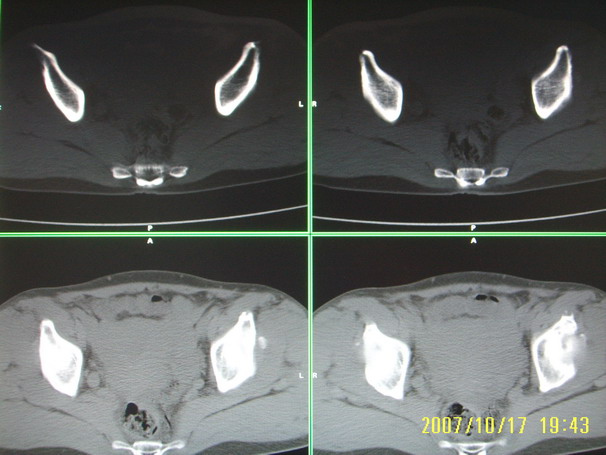

标题: CT10352:女,45岁,股骨头病变,如何诊断? [打印本页]

标题: CT10352:女,45岁,股骨头病变,如何诊断?

股骨头病变,如何诊断?

患者女,45岁,左髋部行走疼痛一年,无外伤史,无感染史。x片示囊状骨透亮区

左侧股骨头变形,密度增高,局部塌陷。多考虑:股骨头缺血性坏死伴退变!

左侧股骨头塌陷,其内囊变硬化,骨纹理改变考虑:左侧股骨头坏死及蜕变.

股骨头形态尚可,骨皮质环厚度及完整性可,病灶区以外骨质尚未见明显异常,临近髋臼骨质亦可见类似改变,考虑退变性关节面下囊变可能性大,骨样骨瘤等不排除,

两侧髋臼结构发育不良伴退行性改变.不除外色素沉着绒毛结节性滑膜炎.

支持成人髋臼发育不良继发髋关节退行性变

髋关节发育不良,左髋关节退变,左髋关节邻关节囊肿

股骨头形态尚可,骨皮质环厚度及完整性可,病灶区以外骨质尚未见明显异常,临近髋臼骨质亦可见类似改变,考虑1.动脉瘤样骨囊肿,2.股骨头缺血坏死,

股骨头形态尚可,骨皮质环厚度及完整性可,病灶区以外骨质尚未见明显异常,临近髋臼骨质亦可见类似改变,考虑退变性关节面下囊变可能性大

双侧股骨头形态都欠规整,外形欠光滑,尤以左侧明显,考虑双侧髋臼发育不良并退行性变